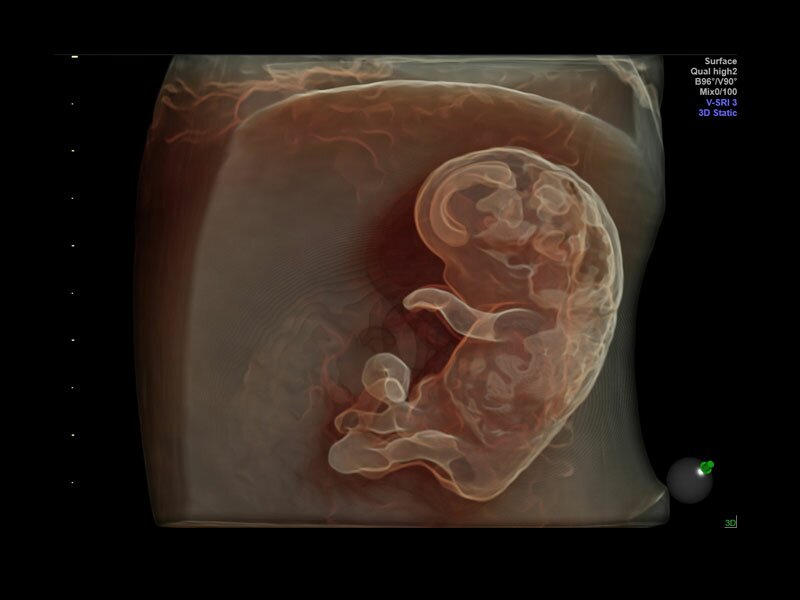

• V-SRI (Volume-SRI) - программное обеспечение для снижения количества артефактов при формировании объемного изображения. Поддерживается датчиками RM6C, RIC5-9, RIC6-12

Объемное сканирование Voluson — 3D/4D вашей мечты

Объемное УЗИ на Voluson E10 — это не просто потрясающе красивая картинка, это ценный инструмент получения дополнительной информации при обследовании женщин.

Voluson E10 поддерживает инновационные технологии формирования изображений — HDlive Silhouette и HDlive Flow, которые позволяют увидеть мельчайшие детали. Алгоритм SonoRenderlive упрощает рабочий процесс и дает возможность реконструировать изображение поверхностей, определяя область перехода между тканью и жидкостью.

• SonoRenderlive

• Улучшает объемную визуализацию за счет автоматического определения линии начала реконструкции при изображении поверхностей. При исследовании в режиме 4D функция SonoRenderlive непрерывно обновляет положение исходной линии с учетом движений плода.